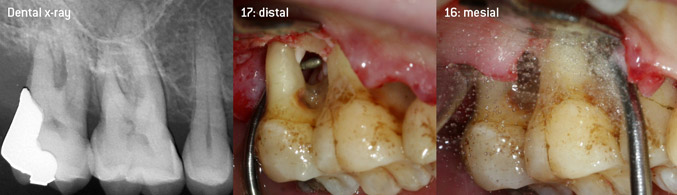

En tant qu'initiateurs du développement du nouvel insert détartreur à air N° 3AP avec un revêtement diamant, les deux dentistes ont reconnu la nécessité d'améliorer les restrictions de manipulation des inserts avec un revêtement diamant disponibles dans le commerce, en particulier lors du traitement des furcations et du travail dans des poches intra-osseuses étroites. Cela devrait être possible pour les procédures non-chirurgicales (figure 2) et chirurgicales (figure 3).

(Photos (Figures 2-4): © Dr. Christian Graetz)

L'objectif était de développer un insert universellement applicable afin d'éviter les changements d'insert qui prennent du temps. En outre, il devrait être plus facile d'utiliser les nouveaux inserts dans les poches intra-osseuses étroites à partir de l'entrée distale et à l'entrée distale de la furcation des molaires maxillaires, ce qui permettrait une utilisation plus efficace des instruments. Pour ce faire, une courbe d'instrument de plus grand diamètre a été utilisée (figure 1), ce qui est très avantageux pour le débridement fermé des dents présentant une perte d'attache avancée et une implication de la furcation en particulier (figure 4).